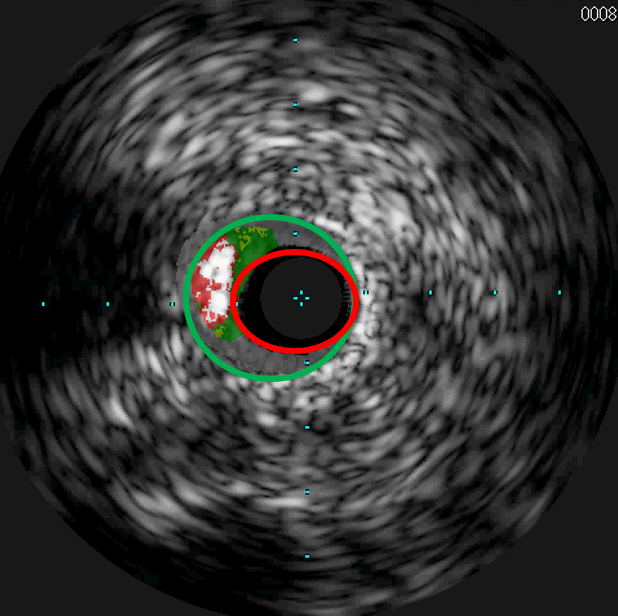

Neben den seit Langem bewährten Stents aus Metall, die lebenslang im Körper verbleiben, werden bei hierfür geeigneten Verengungen auch modernste, resorbierbare Stents (in Fachkreisen auch Scaffolds genannt) auf Magnesiumbasis eingesetzt. Sie lösen sich innerhalb eines Jahres vollständig auf und ermöglichen wieder eine natürliche Gefäßfunktion ohne dauerhaftes Fremdmaterial im behandelten Bereich. Ob eine Engstelle geeignet ist, um mit einem Magnesium Stent versorgt zu werden, wird durch den Einsatz eines Gefäßultraschalls während der Untersuchung geklärt. Eine starke Verkalkung schließt den Einsatz dieser speziellen Gefäßstütze aus.

Der Gefäßultraschall, auch IVUS genannt, zeigt zum einen den ursprünglichen Gefäßdurchmesser (grüner Kreis), zum anderen den noch durchbluteten Anteil des Gefäßes (roter Kreis).